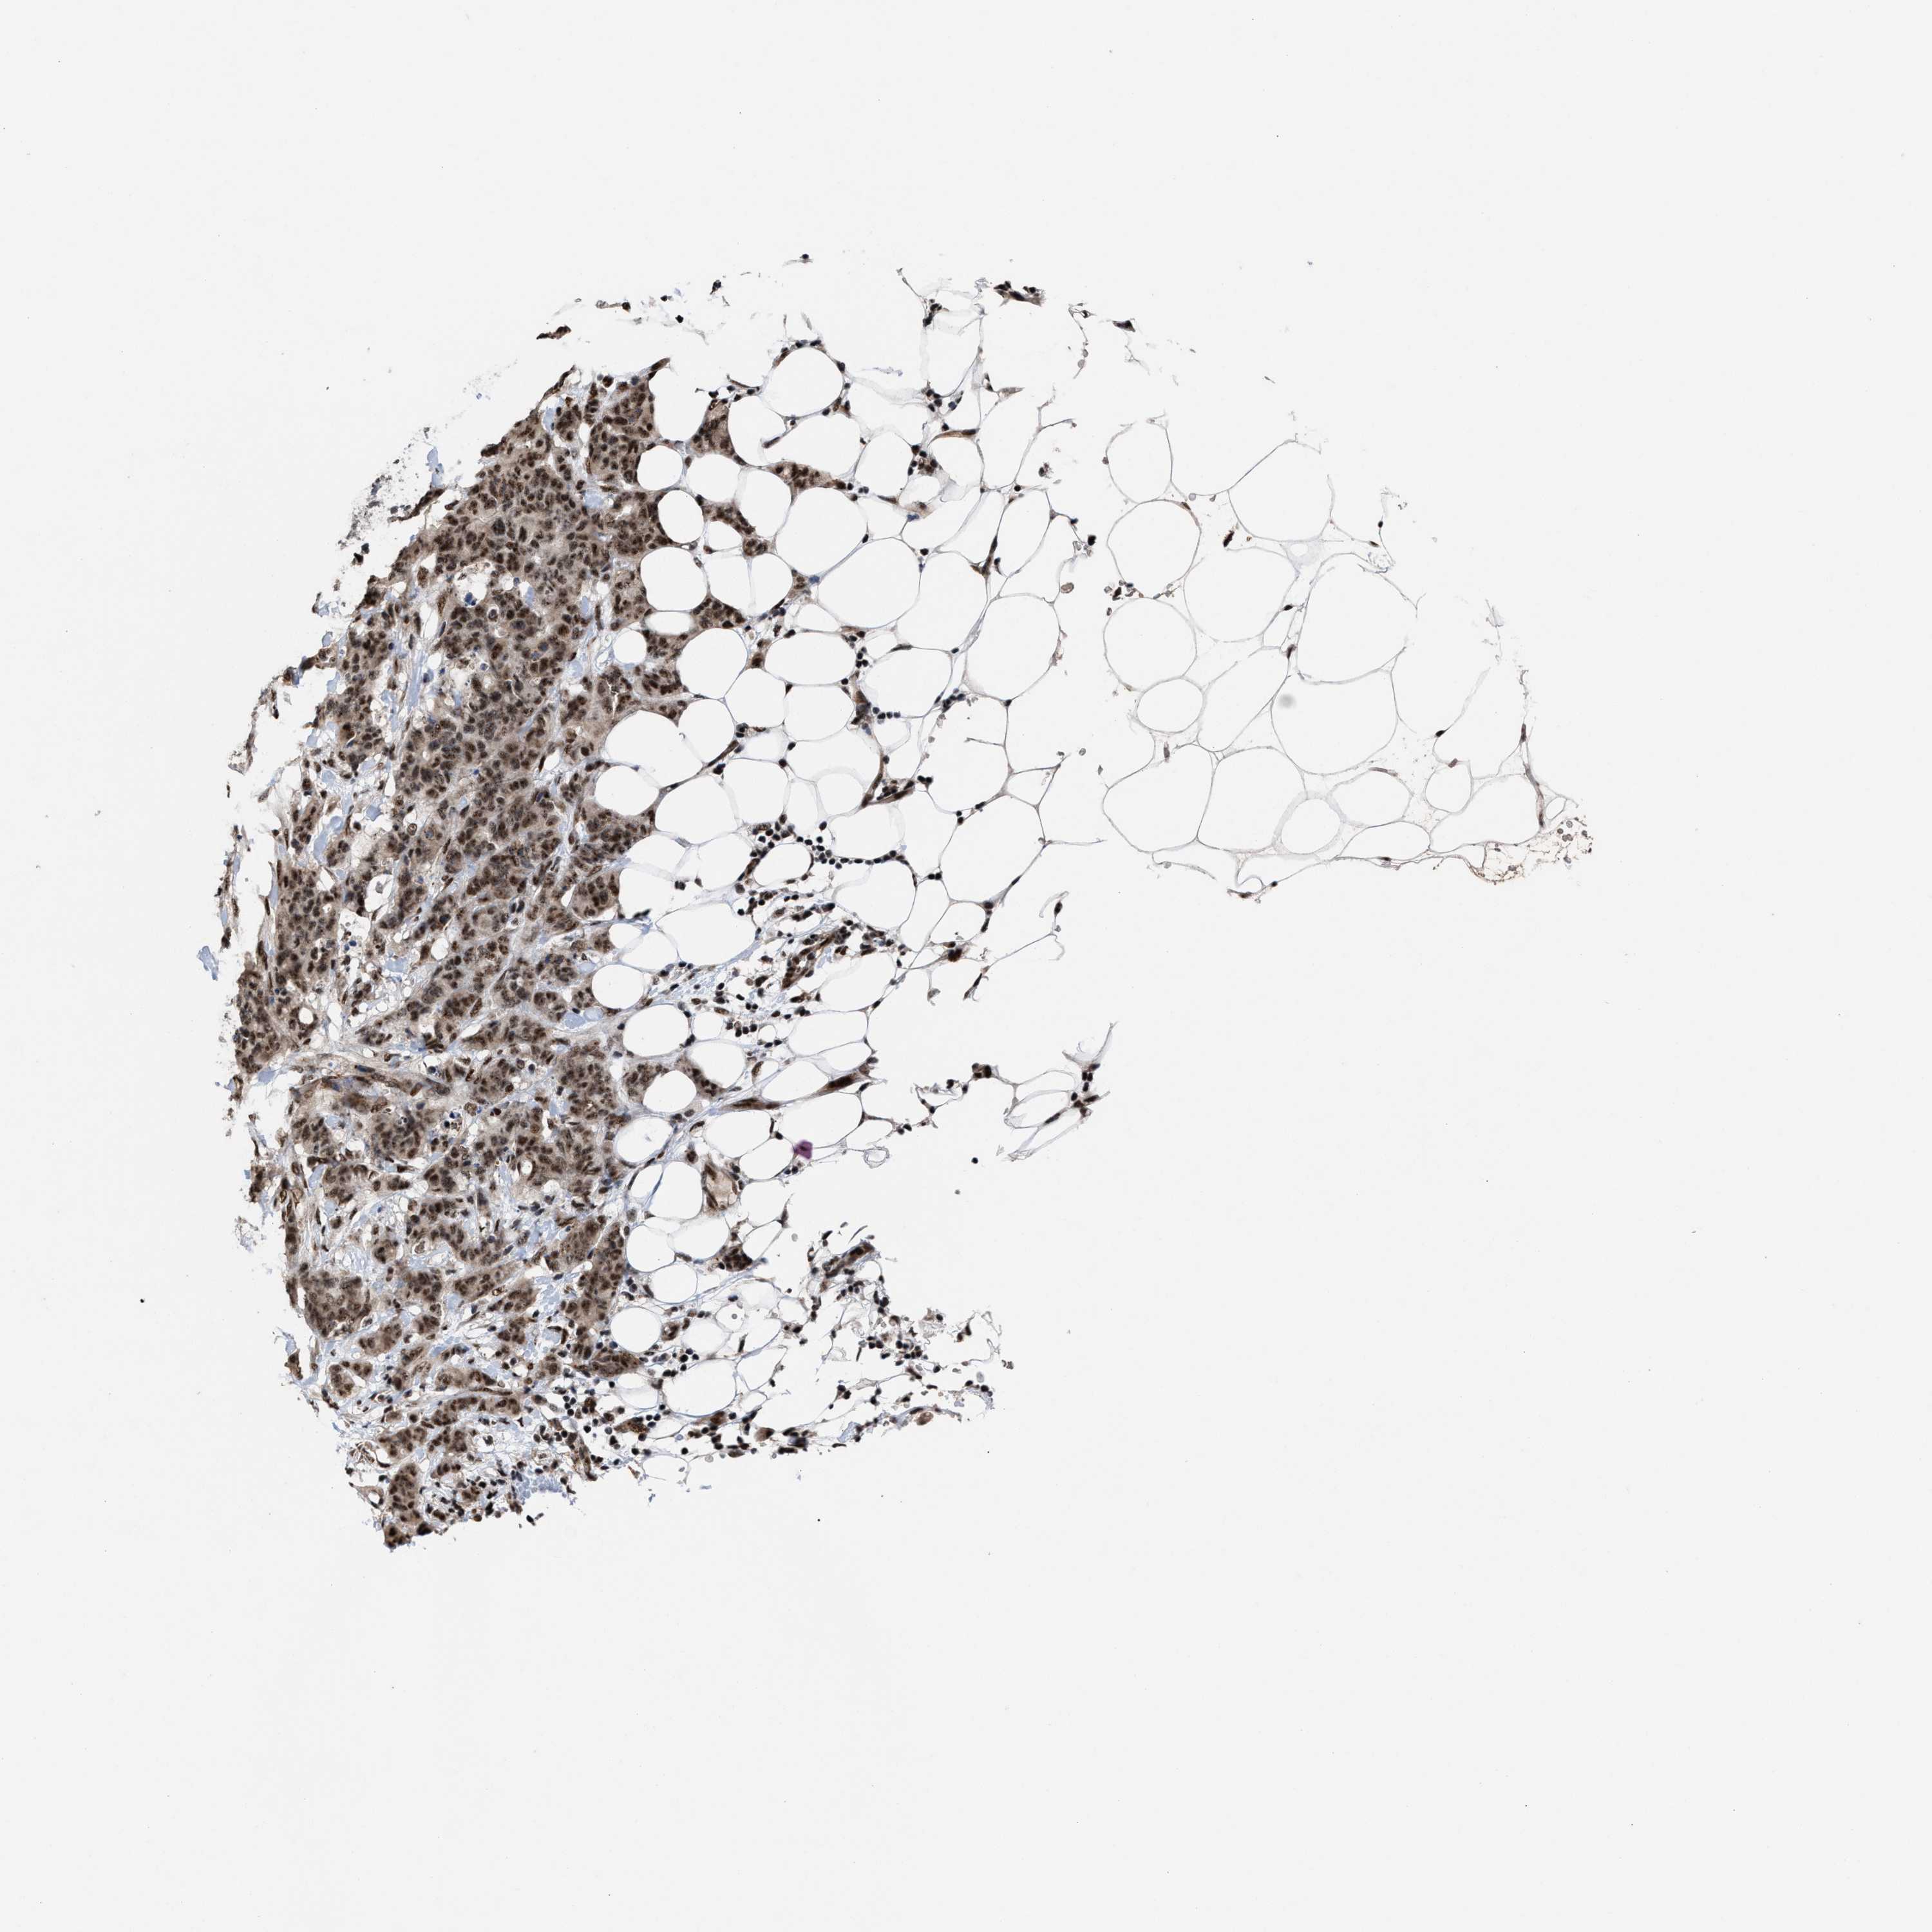

BRCA TCGA BRCA VALIDATION PROTEIN EXPRESSION

ANTIBODIES

AND

VALIDATION